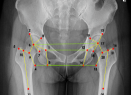

7月21日,在国家骨科与运动康复临床医学研究中心的支持下,解放军总医院骨科医学部陈继营教授、张洪教授、柴伟副教授、张国强...

人工智能 膝关节置换手术 解放军总医院